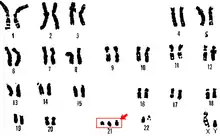

Sex chromosomes

Some of the most frequent genetic disorders are abnormalities of sex chromosomes, but polysomies rarely occur.[18] 49,XXXXY chromosome polysomy occurs every 1 in 85,000 newborn males.[19] The incidence of other X polysomies (48,XXXX, 48,XXXY, 48,XXYY) is more rare than 49,XXXXY.[20] Polysomy Y (47,XYY; 48,XYYY; 48,XXYY; 49,XXYYY) occurs in 1 out of 975 males and may cause psychiatric, social, and somatic abnormalities.[21] Polysomy X may cause mental and developmental retardation and physical malformation. Klinefelter syndrome is an example of human polysomy X with the karyotype 47, XXY. X chromosome polysomies can be inherited from either a single maternal (49, X polysomies) or paternal (48, X polysomies) X chromosome.[18] Polysomy of sex chromosomes is caused by successive nondisjunctions in meiosis I and II.[6]

Giemsa banding (G-banded karyotyping)

Karyotypes are commonly analyzed using Giemsa banding (G-banded karyotyping)). Each chromosome shows unique light and dark bands after they are denatured with trypsin and polysomies can be detected by counting the stained chromosomes. Several cells have to be analysed to detect mosaicism.[53]